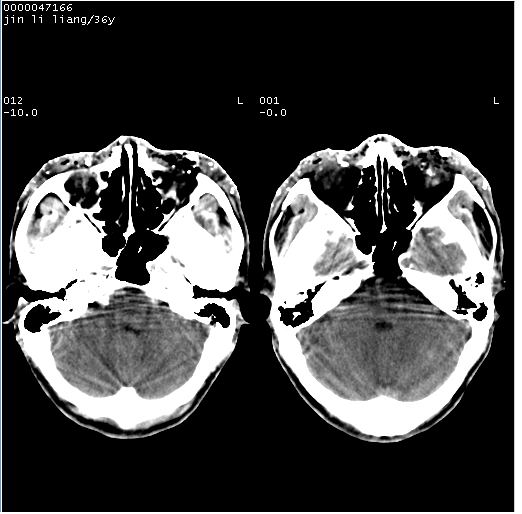

患者 男,36岁。头面部“土炮”炸伤。pe:面目全非,伤口流血不止。

临床诊断:头面部外伤。

颅脑ct轴位平扫(层厚、层距均为10mm),图像如下:

左眼球内容物浑浊其内见气体影,头面部异物.

左眼球破裂积气并异物,眶周、额顶部头皮及软组织挫伤并异物!

迎面一炮,满脸开曝。额顶部头皮及软组织挫伤并异物,左眼球破裂积气并异物,典型的面目全非,惨不忍睹。

左眼球破裂积气并异物,眶周、额顶部头皮及软组织挫伤并异物,右侧眼环前内分异物

1左侧眼球破裂并积气,球内、框内异物。

2额部顶部软组织伤。